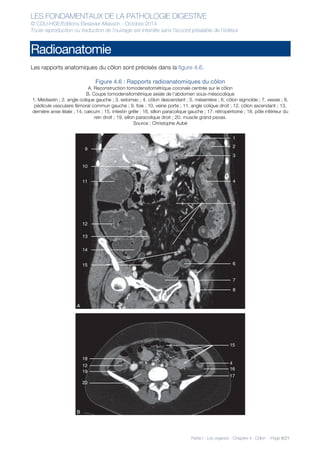

Les rapports anatomiques du côlon sont précisés dans la figure 4.6.

Figure 4.6 : Rapports radioanatomiques du côlon

A. Reconstruction tomodensitométrique coronale centrée sur le côlon

B. Coupe tomodensitométrique axiale de l’abdomen sous-mésocolique

1. Médiastin ; 2. angle colique gauche ; 3. estomac ; 4. côlon descendant ; 5. mésentère ; 6. côlon sigmoïde ; 7. vessie ; 8.

pédicule vasculaire fémoral commun gauche ; 9. foie ; 10. veine porte ; 11. angle colique droit ; 12. côlon ascendant ; 13.

dernière anse iléale ; 14. cæcum ; 15. intestin grêle ; 16. sillon paracolique gauche ; 17. rétropéritoine ; 18. pôle inférieur du

rein droit ; 19. sillon paracolique droit ; 20. muscle grand psoas.

Source : Christophe Aubé